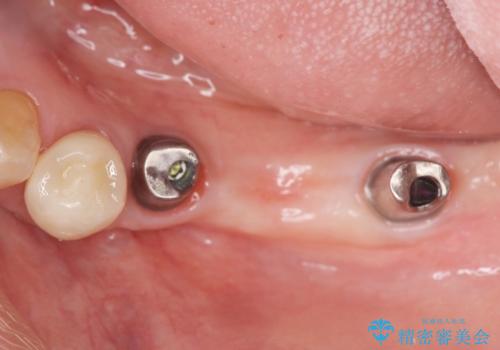

チタンカスタムアバットメントを用いた清掃性の高いインプラント治療

清掃のしやすさと審美性・強度に優れるチタン製カスタムアバットメントとジルコニアクラウンによる補綴治療を計画します。

- 113.3万円(インプラント×2・仮歯×3・チタンカスタムアバットメント×2・ジルコニアクラウン×3)費用は治療当時の料金となります